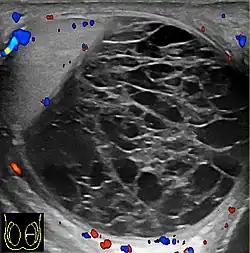

Hemoscrotum can follow trauma (such as a straddle injury) or can be a complication of surgery. It is often accompanied by testicular pain. It has been reported in patients with hemophilia and following catheterization of the femoral artery. If the diagnosis is not clinically evident, transillumination (with a penlight against the scrotum) will show a non-translucent fluid inside the scrotum. Ultrasound imaging may also be useful in confirming the diagnosis. In severe or non-resolving cases, surgical incision and drainage may be required. To prevent recurrence following surgical drainage, a drain may be left at the surgical site.

Current research is ongoing for proper diagnosis and helping to differentiate among other conditions. Doppler ultrasound in a retrospective study was shown to be helpful for differential diagnosis of patients with acute scrotum.[12] Accuracy of imaging studies is higher for the differential diagnosis of testicular torsion and epididmo-orchitis, which there can still be the possibility of misdiagnosis for hematoceles due to testicular torsion.[12] Further research in this area shows importance for surgical decision making in hematoceles.[12]